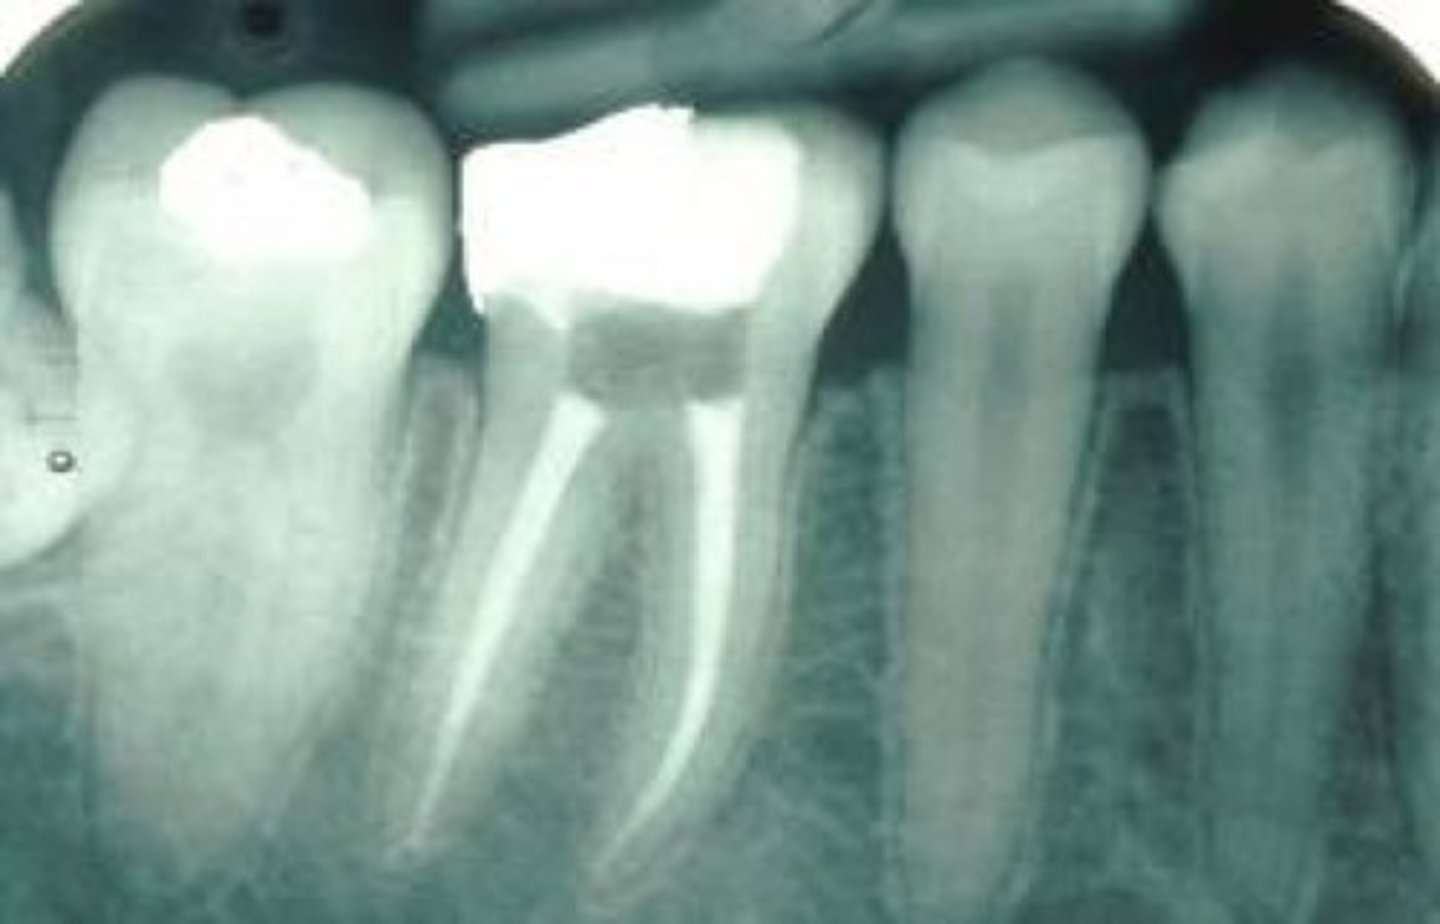

what is used to fill root canals?

gutta percha (zinc oxide)

radiopaque

MOD amalgam

overhang

decay